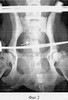

Фиг.2 – рентгенограмма таза животного в процессе стабильной фиксации;

В послеоперационном периоде в течение 28 дней осуществляли стабильную фиксацию отломков крестца с поддержанием условий компрессии на их стыке (фиг.2).